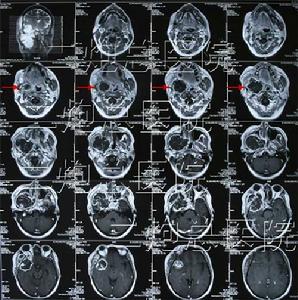

周圍性軟骨肉瘤影像典型,一般不會誤診,甚至可在組織學診斷之前作出診斷。 基本影像是密度增高不透X線的影像,是由於腫瘤內軟骨的鈣化、骨化所引起。與中心性軟骨肉瘤相比,周圍性軟骨肉瘤的鈣化更常見且更廣泛,在許多病例中,這種密度增高的影像幾乎遍布整個腫物。因此,在周圍性軟骨肉瘤中,可看到一骨外腫物,呈模糊分葉狀,表面凹凸不平像花椰菜樣,密度很高。在腫瘤較厚的區域不引起象牙狀的高密度影像,可以看到鈣化無一定的結構,呈典型的結節狀、點狀和環形(相應於軟骨樣的分葉和周邊形成)。腫物表面的鈣化較少,至使腫瘤與軟組織的界限模糊。

在很少見的極早期病例中,周圍性軟骨肉瘤在影像上仍表現為骨軟骨瘤的影像,其惡性演變可通過CT、MRI、大體病理和組織病理而確定,其骨掃描不是在成人期應當的陰性,而是強陽性。 當周圍性軟骨肉瘤位於軀幹骨時,很少能觀察到原存在的骨軟骨瘤痕跡,可能原因是骨軟骨瘤較小或不認識。